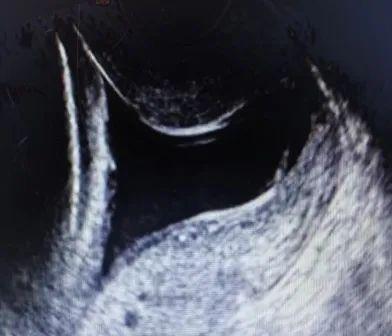

什么是宫颈机能不全?如何诊治?宫颈机能不全临床上主要依据病史、超声检查和典型临床表现进行诊断。1、病史最常见的病史是指孕晚期出现无痛性流产或极早产史;既往有宫颈手术创伤病史,如宫腔镜下子宫纵隔切除术、宫颈锥切术、流产术或引产术等反复机械性扩张宫颈等。2、超声检查超声检查包括经腹、经会阴和经阴道3种方式,指南推荐经阴道超声测量宫颈,也是目前公认的诊断方法,能有效地评估宫颈缩短情况。妊娠24周前宫颈长度≤25 mm,伴有进行性宫颈扩张。非妊娠时,阴道超声测量宫颈长度≤25 mm或8号宫颈扩张棒无阻力地通过宫颈内口。什么是宫颈机能不全?如何诊治?正常闭合宫颈管 什么是宫颈机能不全?如何诊治? 扩张型宫颈管 什么是宫颈机能不全?如何诊治?超声测量宫颈示意图